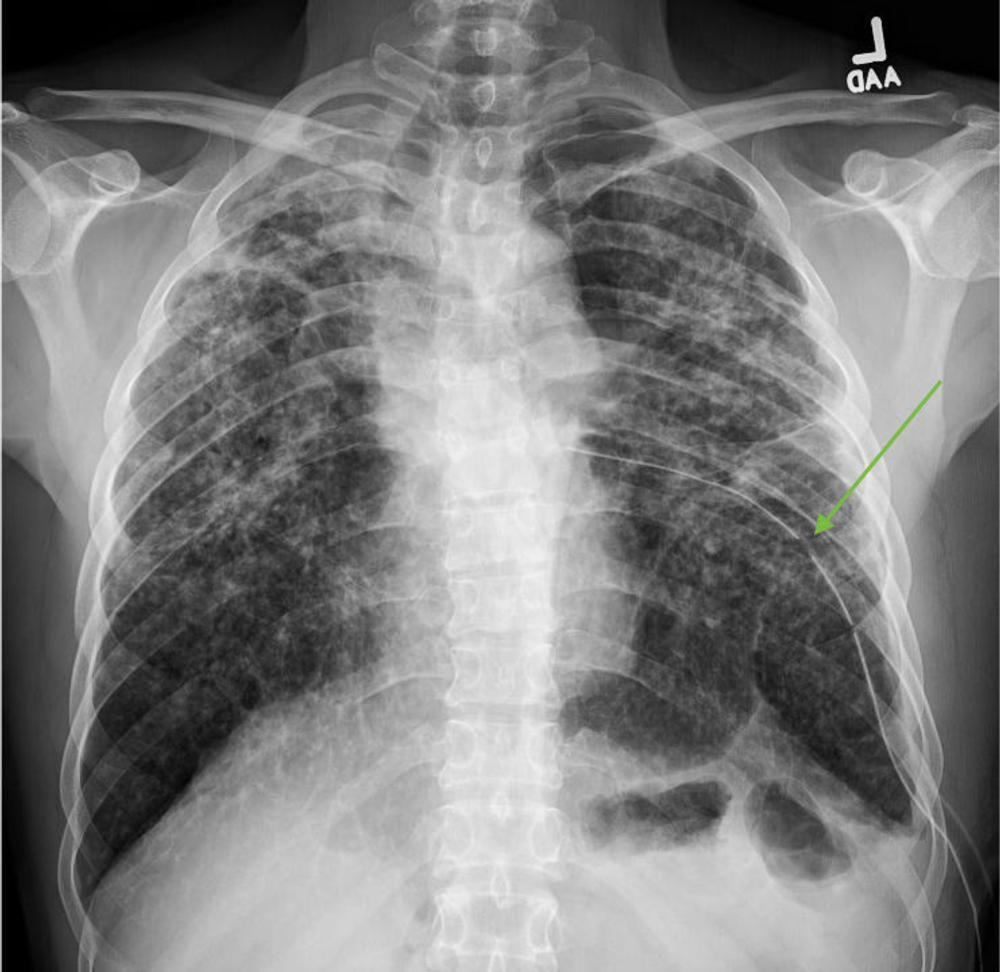

Figure 2. Chest x-ray with placement of a left-sided chest tube (green arrow) and resolution of the tension pneumothorax. There is a background of rounded opacities in the bilateral lung fields, consistent with silicosis.